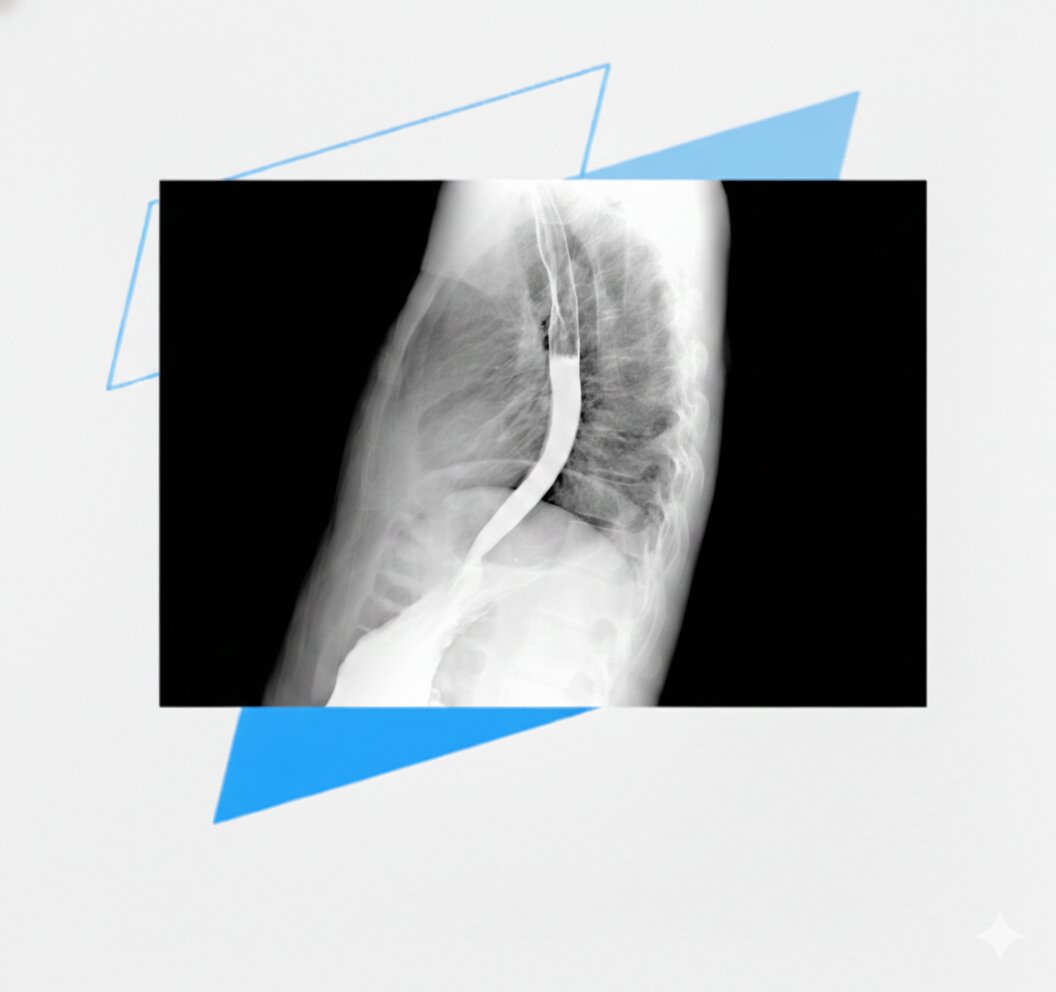

We are developing a Fluoroscopy Simulation module for radiography education and procedural imaging training. The platform is designed to support structured teaching in dynamic X-ray procedures where learners must coordinate patient positioning, beam angulation, collimation and radiation dose management in real time.

Planned procedural coverage includes contrast-based examinations such as barium swallow, oesophagram and upper gastrointestinal fluoroscopy studies. Learners will practise procedural workflow, exposure optimisation and live image interpretation within a controlled virtual environment.

Planned procedural coverage includes contrast-based fluoroscopy examinations such as barium swallow, oesophagram and upper gastrointestinal studies. The module is designed to strengthen competence in live imaging environments where image quality, timing and radiation exposure must be continuously balanced.